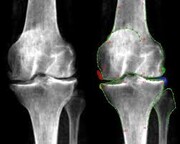

روش درمانی که درد آرتروز زانو را کاهش می دهد

یک مطالعه جدید نشان میدهد افرادی که زانو درد دارند، ممکن است با یک دوره پرتودرمانی با دوز پایین تسکین پیدا کنند.